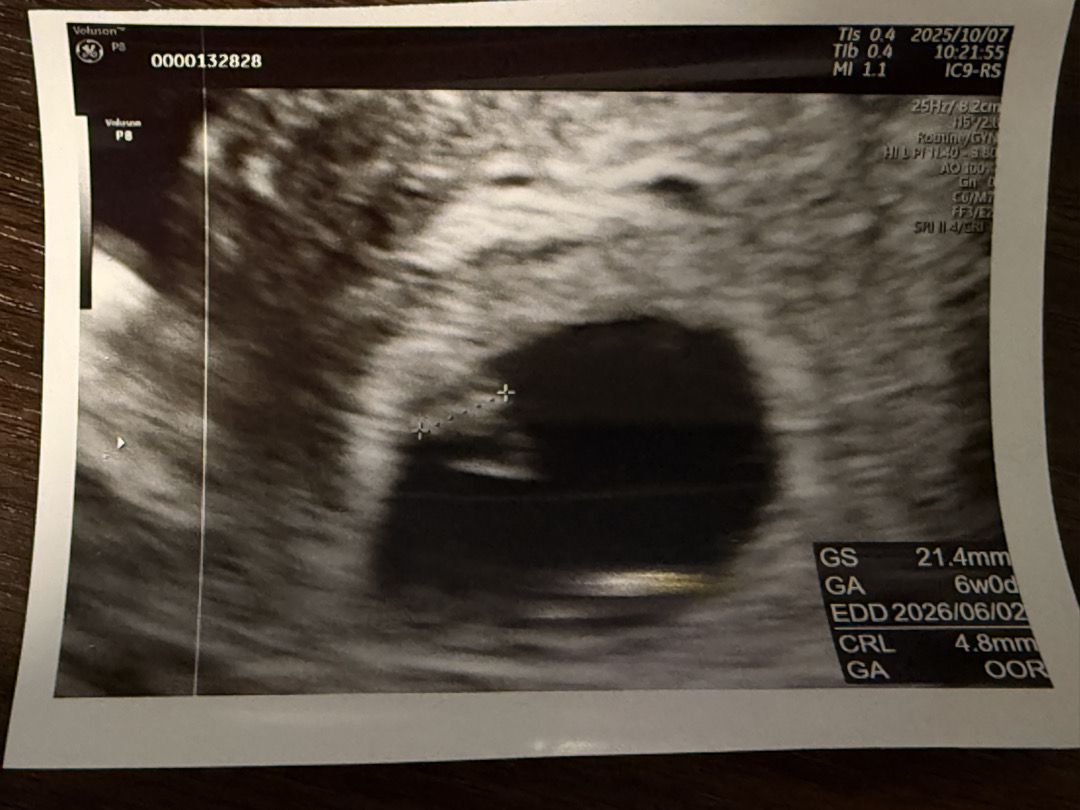

6주0일차 초음파인데 성장이 느린건가요?

옆으로 길다란 타원이 아기라 그랬어요! 저땐 심소 안들려주시더라구요 2주후인 오늘 가서 듣는데 괜히 긴장되네요 성장이 느린건 아니겠죠?